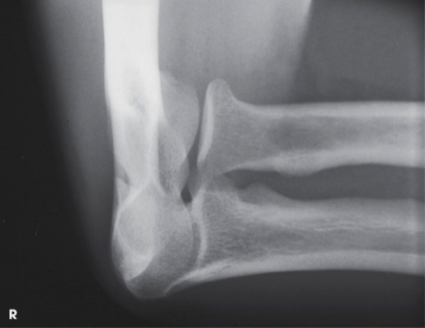

AP oblique elbow, medial rotations

What projection, position, and anatomy is this?